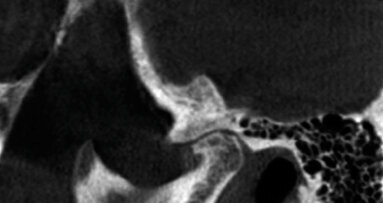

La Cone Beam Computed Tomography (CBCT) sta giocando un ruolo sempre più importante nella diagnosi e nella progettazione del trattamento implantare, e può servire come eccellente strumento preoperatorio prima di procedere al rimodellamento del seno. Quando posizioniamo gli impianti nel mascellare, dobbiamo prendere in considerazione la patologia e l’anatomia dei seni mascellari. Gli studi dimostrano che la prevalenza della patologia mucosa, secondaria a problemi endodontici e parodontali, va dal 5 al 38%. La prevalenza di patologia sinusale trovata con la CBCT in pazienti asintomatici è stata stimata tra il 25 e il 56%. La letteratura concorda sul fatto che un ispessimento della mucosa di circa 1-2 mm è normale.

Mucosite, la patologia più comune del seno, è il termine che indica ispessimento della mucosa e si associa comunemente all’infezione apicale e alle allergie. La secrezione mucosa drena dal seno attraverso l’ostio, che si trova nella parte superiore, e dovrebbe essere distante dalla zona dell’innesto chirurgico; lo svantaggio è che non c’è drenaggio gravitazionale dovuto alla posizione alta dell’ostio. L’altra patologia più comune è la cisti da ritenzione mucosa. Normalmente appare a forma di cupola e di solito è il risultato di un blocco a livello del dotto delle ghiandole mucose. I polipi del seno si formano quando c’è infiammazione e edema nella lamina propria della membrana sinusale. I polipi sono solidi, a differenza delle cisti da ritenzione, che sono ripiene di liquido. Entrambi appaiono radiograficamente simili, sebbene risulti più probabile che i polipi siano peduncolati e che la cisti abbia un’ampia base. Nelle patologie sinusali meno comuni rientra il mucocele, che si forma quando l’ostio è bloccato e il muco si accumula nel seno. I mucoceli tendono a gonfiarsi fino a causare lo spostamento della parete del seno. Quando questo si verifica, è più facile distinguere tra una grande cisti da ritenzione mucosa e un mucocele. Tumori benigni e maligni possono crescere a dismisura e sono in grado di distruggere tutti i margini del seno. Le opacità nel seno possono essere antroliti, osteomi e esostosi. Gli antroliti sono opacità derivanti dalla mineralizzazione intorno a materiale organico e non aderiscono alla parete ossea, mentre gli osteomi e le esostosi sono attaccati alla parete ossea. Infine, qualche patologia può nascere dall’esterno e invadere il seno. Esempi del genere sarebbero le cisti odontogene e le cisti radicolari. Con le modalità di CBCT imaging, la maggior parte delle patologie del seno hanno una opacità simile, il che rende difficile distinguere tra le varie patologie; si dovrebbe porre maggiore attenzione nel valutare la forma e la distribuzione delle lesioni. È quindi fondamentale avere una scansione dell’intero seno fino al piano orbitale, perché è la parte superiore della lesione che consente la definitiva diagnosi differenziale (ad esempio a forma di cupola, dritta o curvilinea). Una scansione completa dei seni aiuta anche a stabilire se l’ostio è bloccato. Un ostio bloccato avrà una maggiore probabilità di morbilità conseguente a chirurgia implantare poiché non sarà in grado di drenare adeguatamente batteri e detriti. Va fatto notare che devono essere rinviati tutti i pazienti con segni di patologia sinusale, che debbano fare o no innesto osseo o impianti.